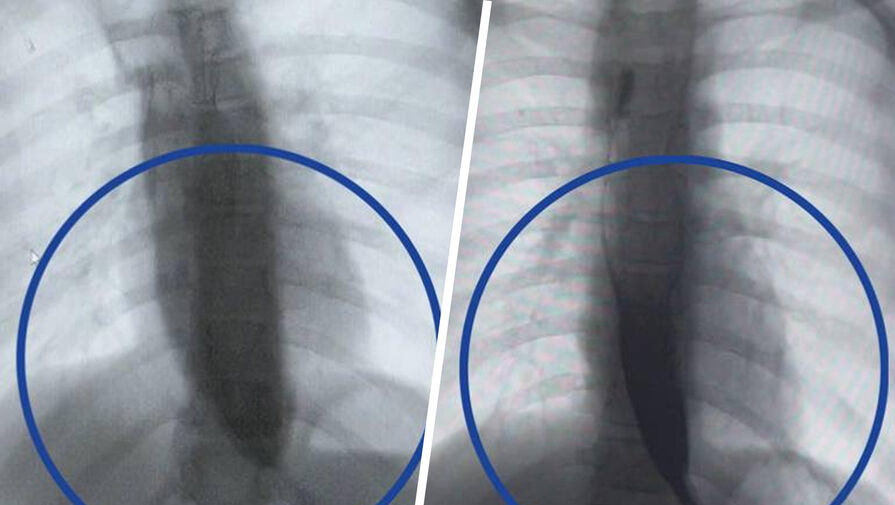

Врачи Детского клинического центра им. Л.М. Рошаля спасли девятилетнюю девочку с редким заболеванием — ахалазией кардии, из-за которого ее пищевод был расширен в пять раз. Об этом сообщили в пресс-службе минздрава Московской области.

Медики рассказали, что пищевод пациентки из-за патологии был расширен до четырех сантиметров, при норме в семь — десять миллиметров.

«Мы через разрез в пищеводе создали подслизистый туннель и рассекли циркулярные мышцы, блокирующие проход пищи», — поделился заведующий отделением эндоскопических методов диагностики больницы Александр Иноземцев.

Операция прошла успешно, что уже на следующий день показало контрастное исследование — пища стала беспрепятственно поступать в желудок.